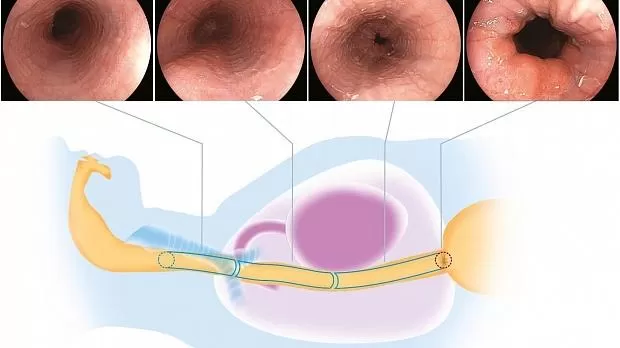

Пищевод

В пищеводе верхняя треть исследуется путем размещения телескопа на естественной оси, где левый главный бронх ориентирован на 9–12 часов, область 2. Удовлетворительное изображение верхней трети захватывает левый главный бронх как дистальная ссылка. Средняя треть оценивается путем сохранения той же оси и фиксации ориентира левого предсердия, что и дистального ориентира, области 3. Затем эндоскоп продвигается дистально, сохраняя ту же ориентацию, а нижняя треть захватывается после прохождения ориентира левого предсердия с помощью EGJ. часто используется в качестве дистального ориентира, область 4 (рис. 2 ).